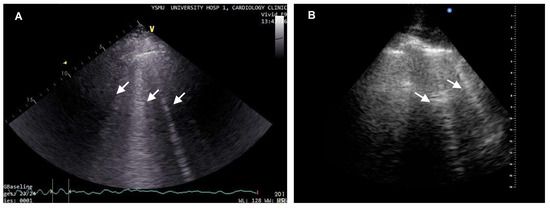

3. Speckle Tracking